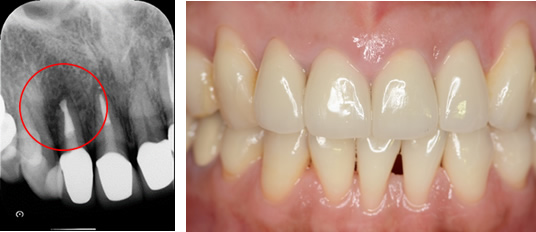

X線写真です。赤丸に大きな病巣があります。

術直後のレントゲンです。

治療後

病巣(赤丸)は消失しています。

どんなに根の治療が良好になっても、被せものが歯とあってないと(不適合補綴物)、上部から感染をおこし失敗してします。よって精度の高いジルコニアオールセラミッククラウンで治しました。